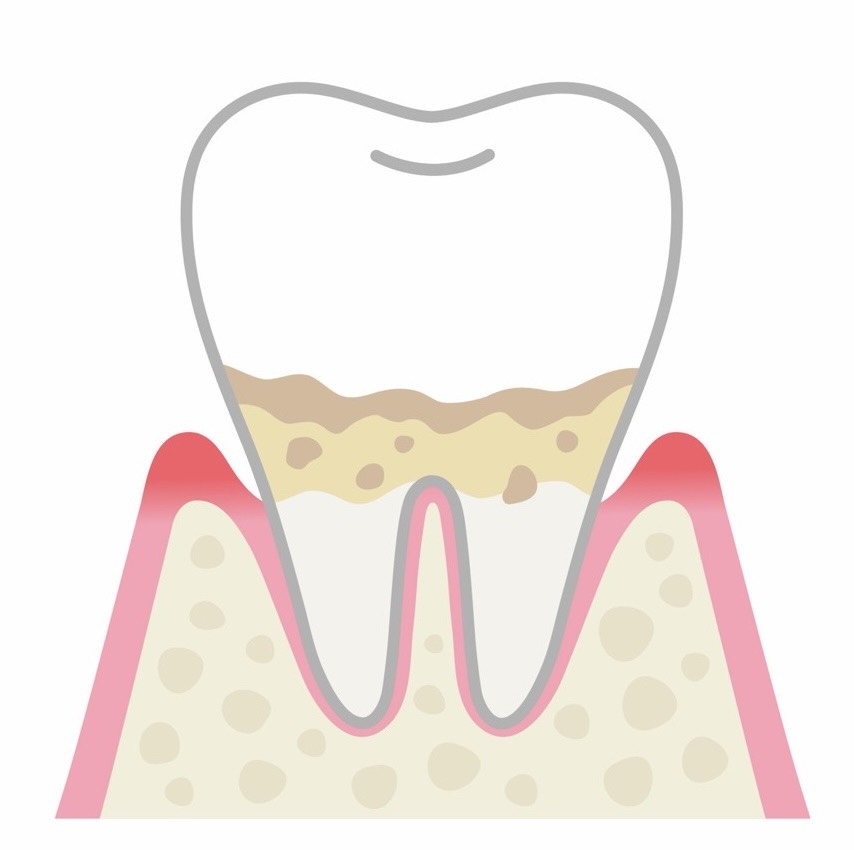

歯肉炎(初期段階)

歯茎だけに炎症が起きている状態で、歯を支える骨にはまだ影響が及んでいません。歯茎が赤く腫れたり、歯磨きのときに出血したりすることがあります。この段階であれば、適切なブラッシングと歯のクリーニングによって、元の健康な状態に戻すことが可能です。

軽度歯周炎

歯茎の炎症が進み、歯と歯茎の間の溝(歯周ポケット)が深くなり始めます。歯を支える骨も少しずつ溶け始めており、歯茎の腫れや出血が頻繁に見られるようになります。口臭が気になり始めることもあります。この段階では、歯石の除去と丁寧なブラッシング指導が必要です。